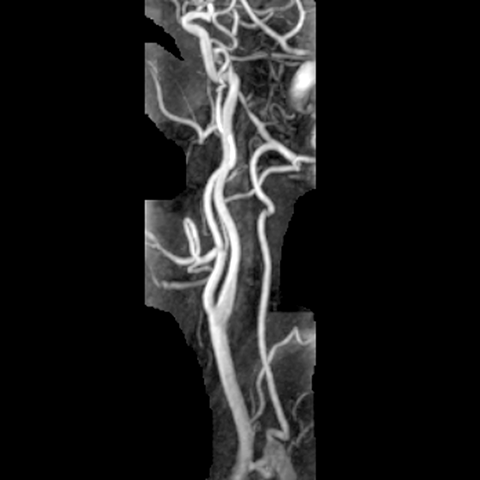

Carotid arteries (normal) [4 of 5]